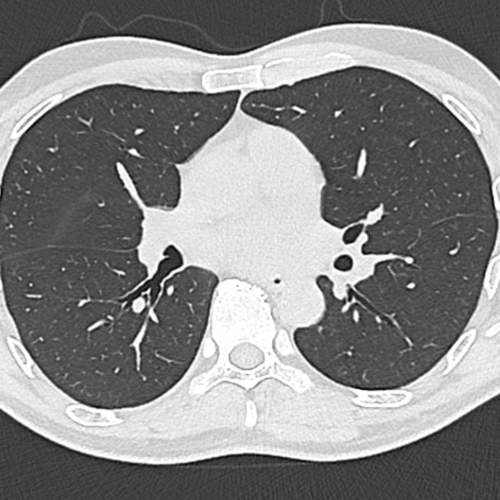

Cet examen est réalisé pour analyser le thorax.

Cette technique de visualisation des poumons est réalisée en cas de toux, de suspicion d’infection pulmonaire, de suspicion de cancer des poumons, notamment chez les patients fumeurs. Cela permet également le diagnostic d’embolie pulmonaire (caillot dans les artères pulmonaires)

La TDM thoracique permets également d’analyser les tissus autour du poumon, le médiastin (contient coeur, trachée, gros vaisseaux, oesophage) , la plèvre et les côtes notamment.

Cet examen ( TDM thoracique )  permets de diagnostiquer:

• des nodules qui font suspecter un cancer des poumons.

• une pneumopathie ou pneumonie (infection des poumons)

• une bronchite (inflammation des bronches)

• une dilatation des bronches et bronchocèles ( infection dans les bronches)

• de l’emphysème (destruction du parenchyme pulmonaire par le tabac)

• une fibrose pulmonaire (épaississement fibreux du poumon)

• une pleurésie (épanchement de liquide dans la plèvre)

• un pneumothorax (décollement gazeux de la plèvre)

• Une embolie pulmonaire (caillot des artères pulmonaires)

• un anévrysme de l’aorte thoracique (dilatation de l’aorte thoracique)

• des adénopathies médiastinales (ganglions anormaux du médiastin)

• des fractures costales en cas de traumatisme

• des fractures vertébrales

• des lésions osseuses vertébrales